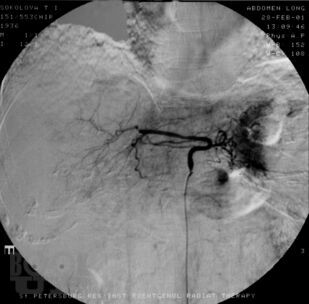

В монографии проанализированы данные литературы и собственные результаты лечения более 700 больных (1983- 2001) первичным и метастатическим раком печени. Дан обзор наиболее часто применяемых рентгеноэндоваскулярных вмешательств. В случае нерезектабельного поражения внутрисосудистая терапия включает регионарную химиоинфузию, эмболизацию, химиоэмболизацию печеночной артерии и воротной вены. Оценены возможности указанных рентгеноэндоваскулярных вмешательств, а также предоперационной механической эмболизации воротной вены при резектабельных опухолях. Рассмотрена роль адъювантной локорегионарной терапии после выполнения резекции печени. Сделано заключение о том, что рентгеноэндоваскулярные вмешательства играют важную роль в лечении злокачественных опухолей печени. Комбинированный подход к лечению злокачественных новообразований печени позволяет расширить возможности оказания помощи больным и добиться улучшения отдаленных результатов.